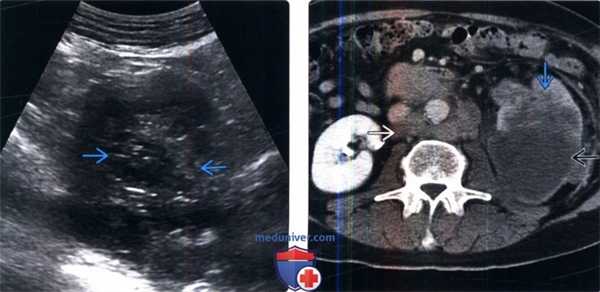

(Слева) УЗИ левой почки в поперечной плоскости: выявлено замещение нормальной жировой клетчатки почечного синуса нечетко определяемым мягкотканным образованием, предположительно переходноклеточным раком.

(Справа) КТ с контрастированием, нефрографическая фаза, аксиальная проекция: у этого же пациента обнаружено образование с гетерогенным контрастированием, сглаживающее границы синуса и прорастающее в паренхиму почки. Обратите внимание на метастатическую забрюшинную лимфаденопатию.